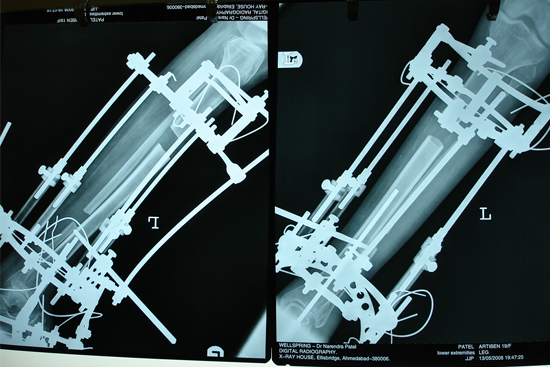

Limb Lengthening

TEV

Dr. J.J. Patwa has entitled "MASTER CASES OF ILIZAROV" and He has also vast experience of 35 years in the field of orthopaedic.

has Done Highest No. of Cases in the World like 5000 Cases in Polio, 267 Cases in H-Q Transfer, 72 Cases in Peroneal Translocation, 50 Cases in Infected Gap Non-Union of Femur and 60 Cases in Followup of Burgers Disease.